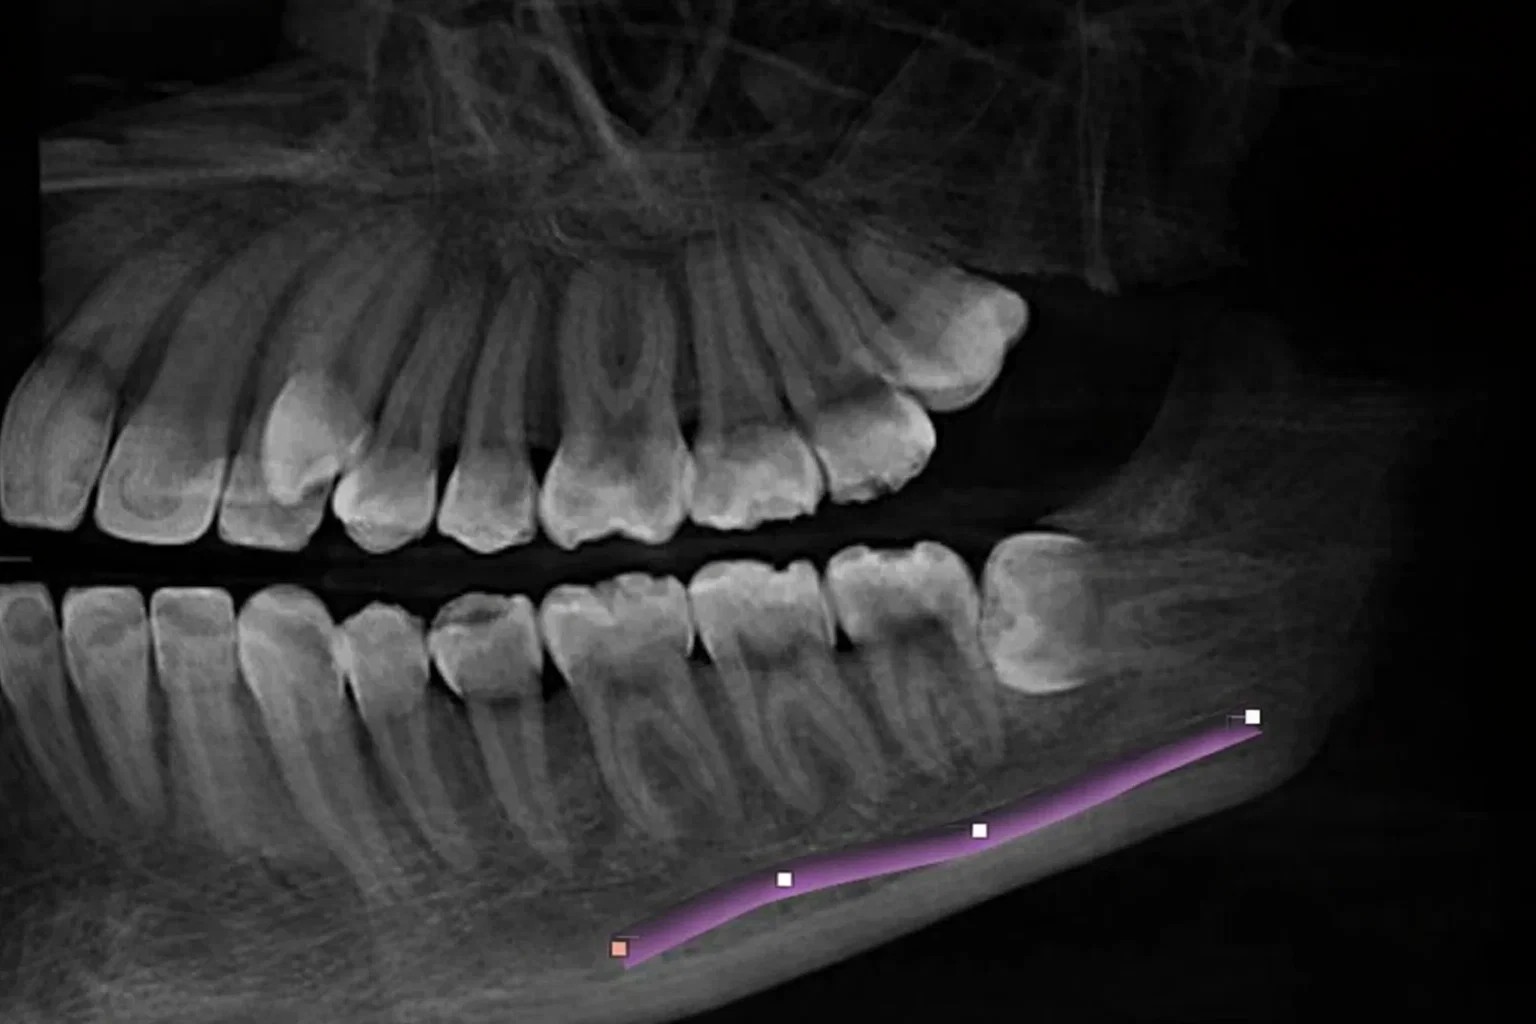

서울 치과 신경 손상 걱정 없는 3D CT 정밀 진단

아래턱 매복 사랑니는 아래 입술과 턱의 감각을 담당하는 ‘하치조신경’과 매우 가깝게 위치합니다. 2D 엑스레이에 의존하는 것이 아닌 3D CT를 통해 신경의 위치와 뿌리 형태를 입체적으로 분석합니다.

디지털 장비로 0.1mm 단위까지 정밀 분석하여 신경 손상 가능성을 최소화하고, 최소 절개와 분할 발치 기법을 통해 통증과 부기를 현저히 줄인 안전한 발치를 진행합니다.